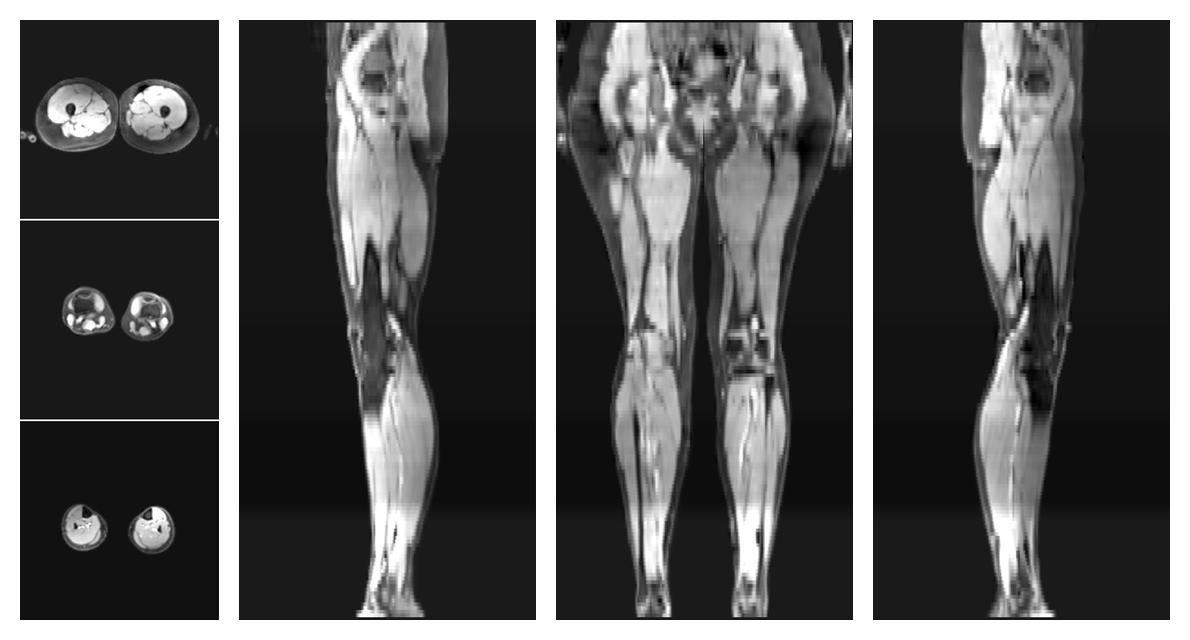

• Mean diffusivity

IVIM corrected whole leg muscle mean diffusivity obtained from diffusion tensor imaging.